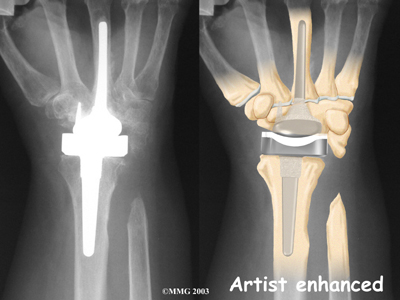

Modern artificial wrist joints are made of metal and plastic. The part that fits against the end of the radius bone of the forearm is called the radial component. It is made up of two pieces. A flat metal piece is placed on the front part of the radius. It has a stem that attaches down into the canal of the bone. A plastic cup fits onto the metal piece, forming a socket for the artificial wrist joint.

The part that replaces the small wrist bones is called the distal component. This piece is made completely of metal. It is globe shaped to fit into the plastic socket on the end of the radius. The metal distal component is attached by two metal stems that fit into the hollow bone marrow cavities of the carpal and metacarpal bones of the hand.

The plastic used in artificial joints is tough and slick. It allows the two pieces of the new joint to glide easily against each other as you move your wrist. The ball and socket allow movement of the wrist in all directions.

Replacement Joint

The surgeon will take some time to get the stems to fit tightly. The joint is put in place and tested through its range of motion to make sure it moves correctly. Once the surgeon is satisfied with the fit, the stems of each metal implant are:

Cemented into Place